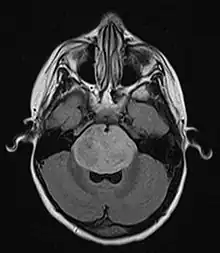

![]() | |

| Brain stem glioma. MRI axial, with contrast | |

A brainstem glioma is a cancerous glioma tumor in the brainstem. Around 75% are diagnosed in children and young adults under the age of twenty, but have been known to affect older adults as well.[1] Brainstem gliomas start in the brain or spinal cord tissue and typically spread throughout the nervous system.[2]

Neuroimaging, such as MRI, is the main diagnostic tool for brain stem gliomas. In very rare cases, surgery and biopsy are performed.